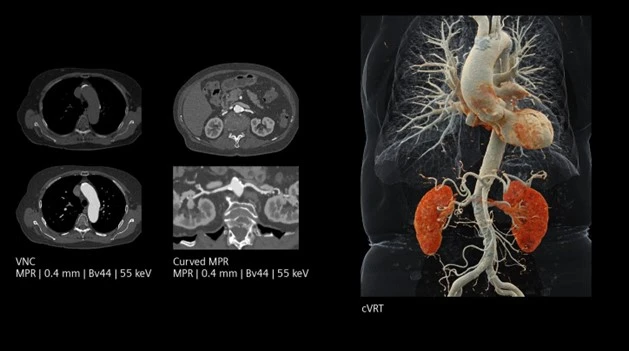

- Thu nhận đa mức năng lượng trong một lần quét: Photon được phân loại vào nhiều mức năng lượng khác nhau (energy binning), tạo ra dữ liệu phổ đa năng lượng đồng thời mà không cần bóng tia X kép hay bộ lọc cơ học như CT hai mức năng lượng thế hệ trước.

- Phân tách vật chất (material decomposition): Dựa trên sự phụ thuộc năng lượng của hệ số suy giảm, PCCT cho phép phân biệt chính xác iodine, canxi, mỡ và mô mềm…

- Tối ưu liều tia và thuốc cản quang: SNR cao cho phép giảm liều bức xạ và giảm liều thuốc cản quang, góp phần hạn chế nguy cơ suy thận và các tác dụng không mong muốn.

Hô hấp

- CT phổi độ phân giải rất cao: giúp phát hiện sớm bệnh phổi kẽ, tổn thương kính mờ, tiểu phế quản…

- Đánh giá khí phế thũng bằng cách định lượng phân bố không khí và bản đồ mật độ nhu mô phổi với độ tin cậy cao.

(Courtesy of Diagnostikum Graz, Austria)